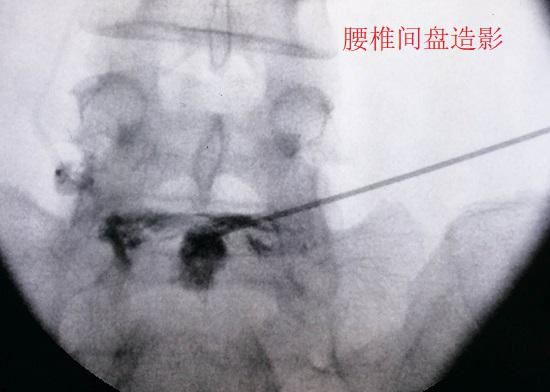

所谓轴性下腰痛,是指单纯的、且疼痛位置集中于腰椎附近的下腰背疼痛。轴性下腰背疼痛患者首先要进行至少6个月的保守治疗,在保守治疗无效的情况下,还可以考虑通过介入的方式对疼;�󬽧痛部位进行封闭治疗或阻断治疗。如果都没有效果且疼痛难以忍受,应通过影像学检查、椎间盘造影(以诱发疼痛)等手段进行诊断,在确定存在退变且疼痛部位与退变节段相关时,方考虑针对退变节段实施融合手术。

腰椎间盘造影